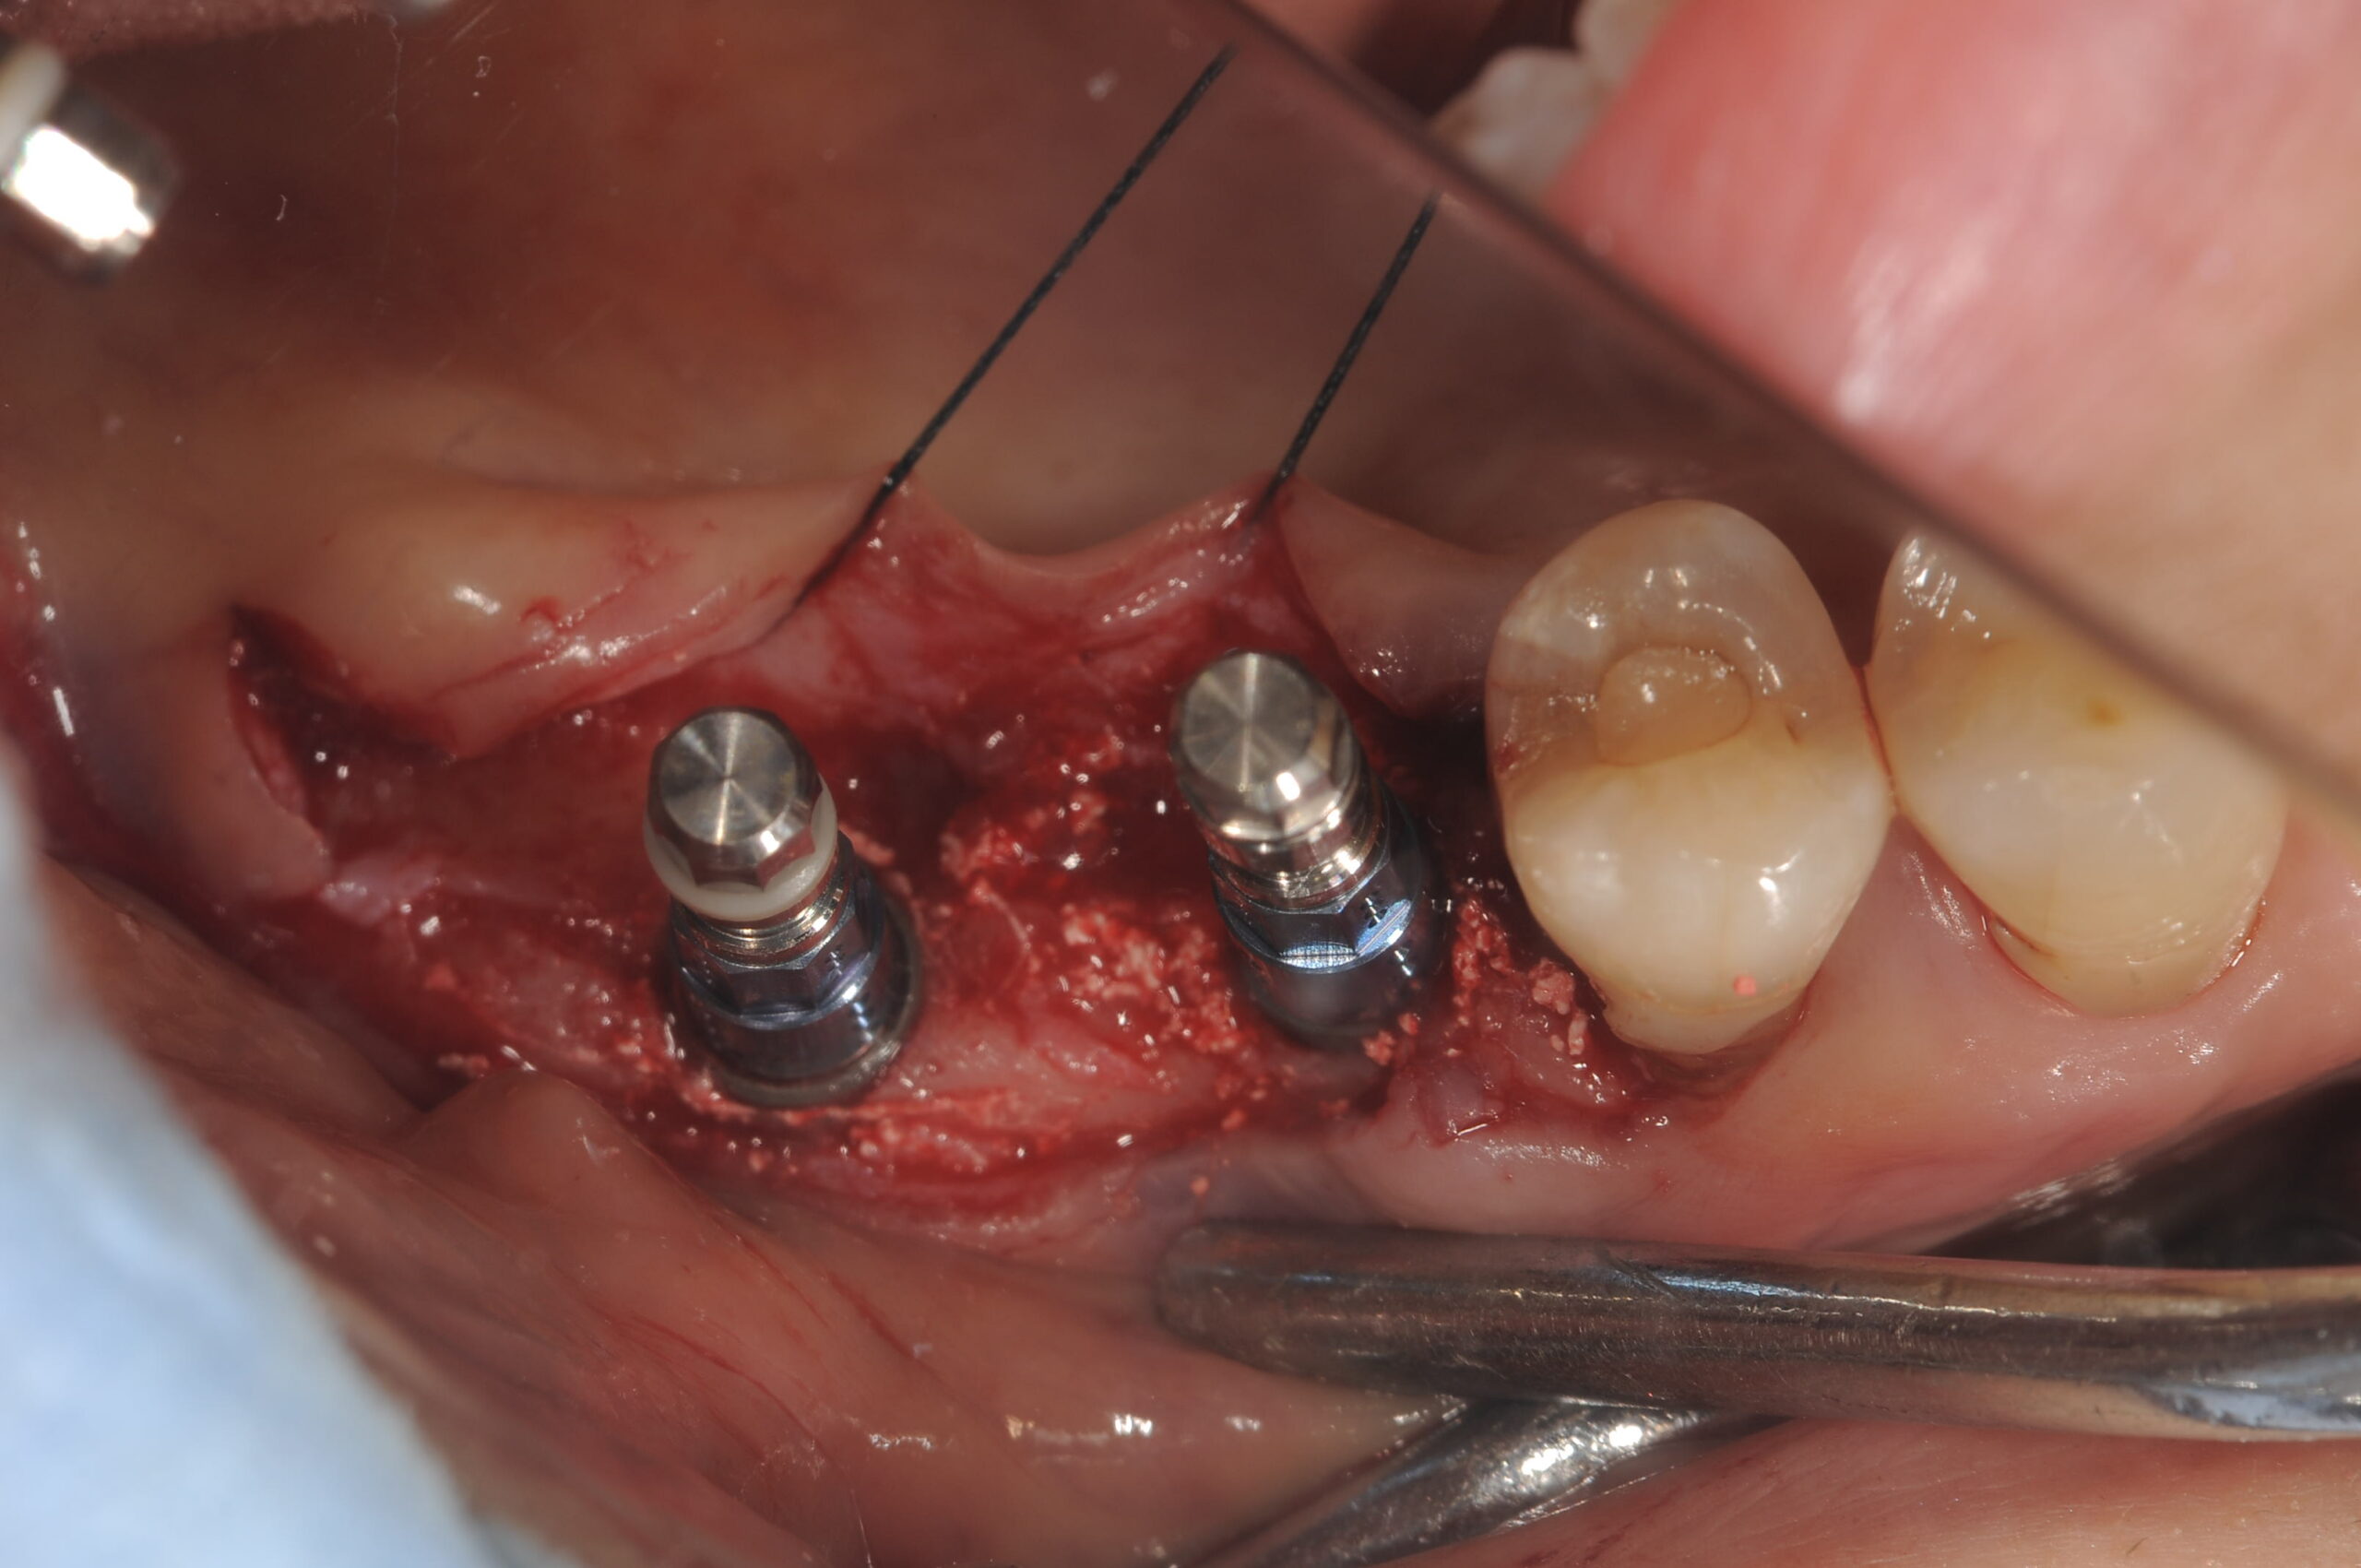

初期固定も充分でしたので、1回法で埋入できています。

オステオトームテクニックでソケットリフトをしていきます。

ストローマンボーンレベルRCのSLActiveの4.1mmと4.8mmを用いました。

術後の所見ですが、ポジショニングもまずまずですね。